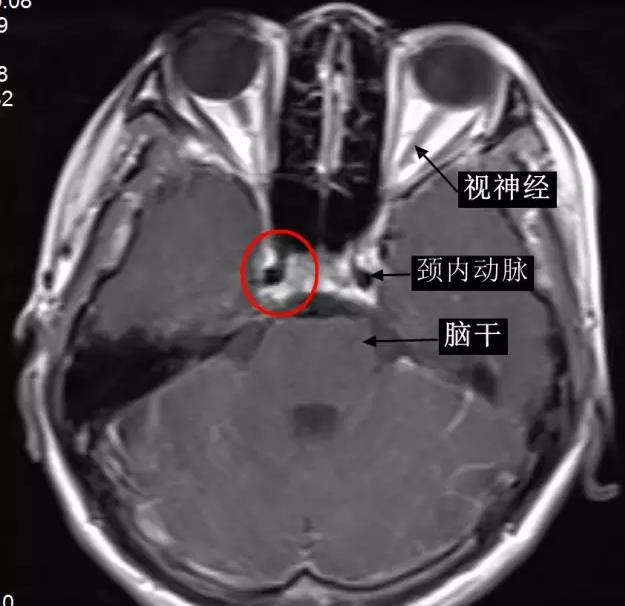

海綿竇位置影像顯示 (橫斷面),增強磁共振圖像(下圖中紅圈內高信號區即右側海綿竇)